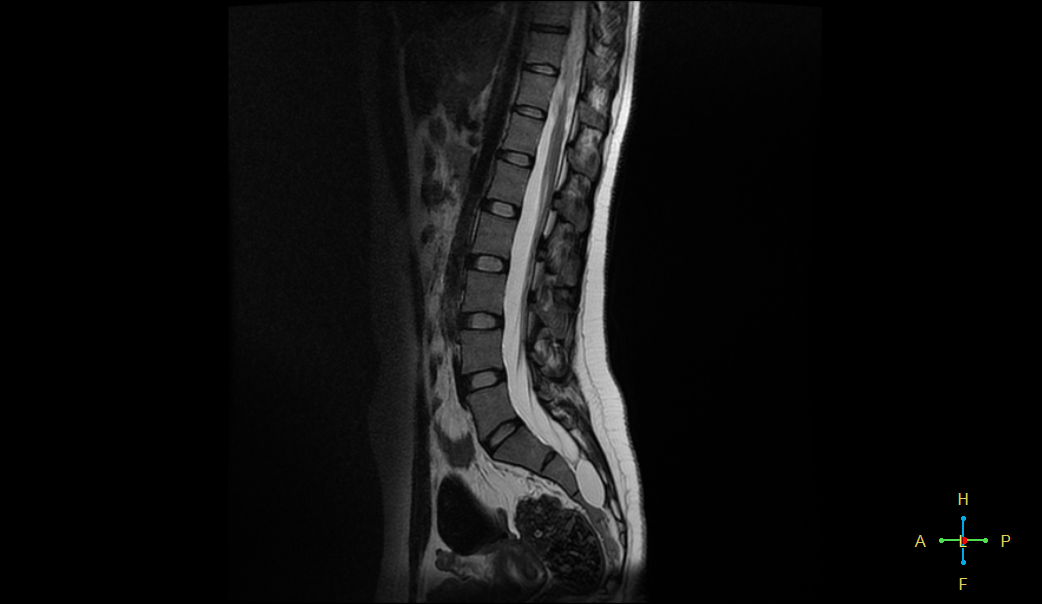

تبين بصورة الرنين وجود كيس في المنطقة العجزية حجمه ٣ سم وأكثر بقليل

هذه الالام مفسرة من الكيسة وضغطها على الاعصاب

وهي لا تستجيب على الادوية ويفضل استصالها جراحيا